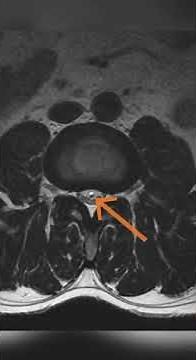

Filum Terminale MRI

Filum Terminale Lipoma

Filum terminale of spinal cord